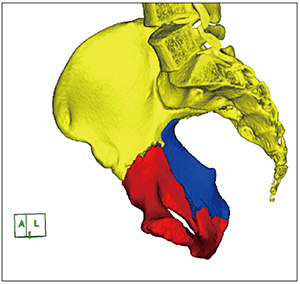

抽出された骨片をそれぞれ入力1,2,3に設定し,色分けを行う(図2)。回転および移動を用いて骨片整復シミュレーションを行う。この時,多方向から観察することで骨片整復が正確に行えているかを確認する(図3)。さらに,インプラントデータを骨折部に重ねることで,必要なプレート長,ベンディング部位をあらかじめ決めておくことができる。複雑な形状をとる骨片を色分けすることで,術前カンファレンスにおける指導医から助手への手術工程の確認や,術中の助手に対する指示を明確にすることができる。また,プランニングにおいてはスクリュー長を計測することも可能であり,術中のデプスゲージの計測値と比較することで適切な位置や角度で挿入できているかの指標になる(図4)。

図2 抽出した骨片ごとに色分け |